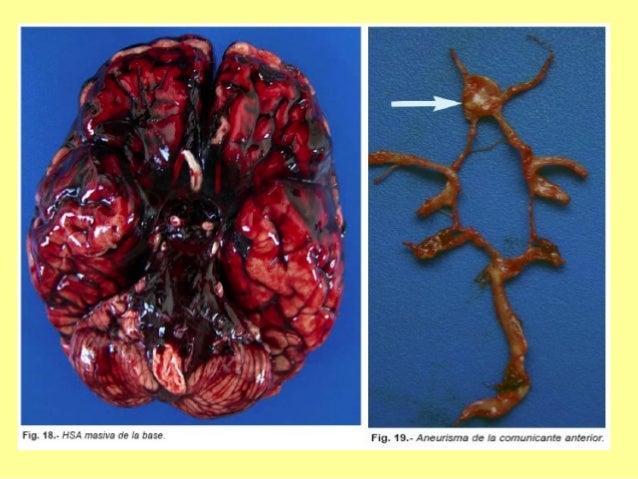

28. 28. HIPE HEMORRAGIAINTRAVENTR.ANGIOPATIAAMILOIDEA.